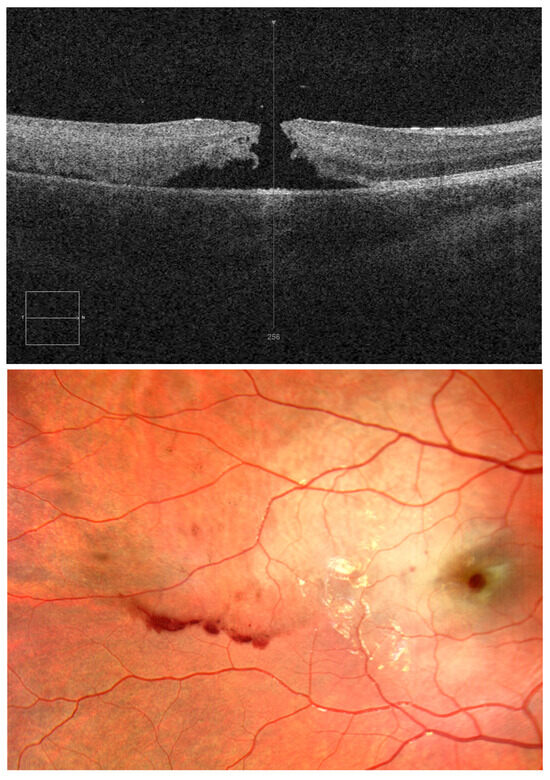

Figure 2. OCT and OD fundus images on day 10 after injury. The child was treated with systemic methylprednisolone, rutoside, and ascorbic acid. Dexamethasone eye drops, ophthalmic diclofenac, dorzolamide, troxerutin, and atropine sulphate were applied to the right eye. After a 10-day hospital stay, visual acuity in the right eye was still 0.04; intraocular pressure was 21 mmHg. OCT revealed closure of the macular hole but disorganised retinal inner layers and a small central fluid space in the macula (Figure 2). The child did not complain of right eyeball pain but remained concerned about poor visual acuity in the right eye.